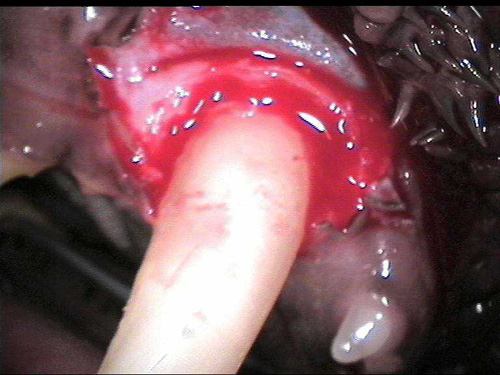

CL1-3